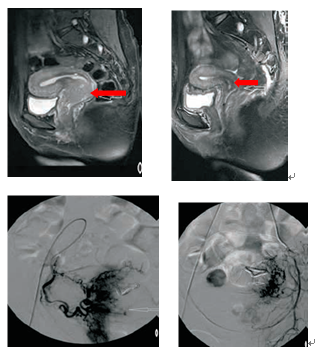

宫颈癌Ⅲb期(巨块型),介入治疗联合放疗后四个月,肿瘤近乎消失